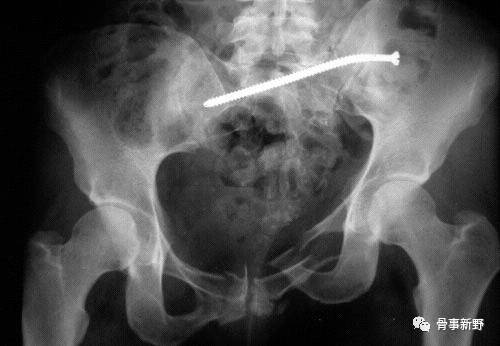

垂直不稳(术前)

垂直不稳复位、固定(术后)

垂直不稳再移位、螺钉扭曲(术后)

通过置入第二枚螺钉,或与其它固定方式组合,构成三角固定,可明显增加后环稳定性。